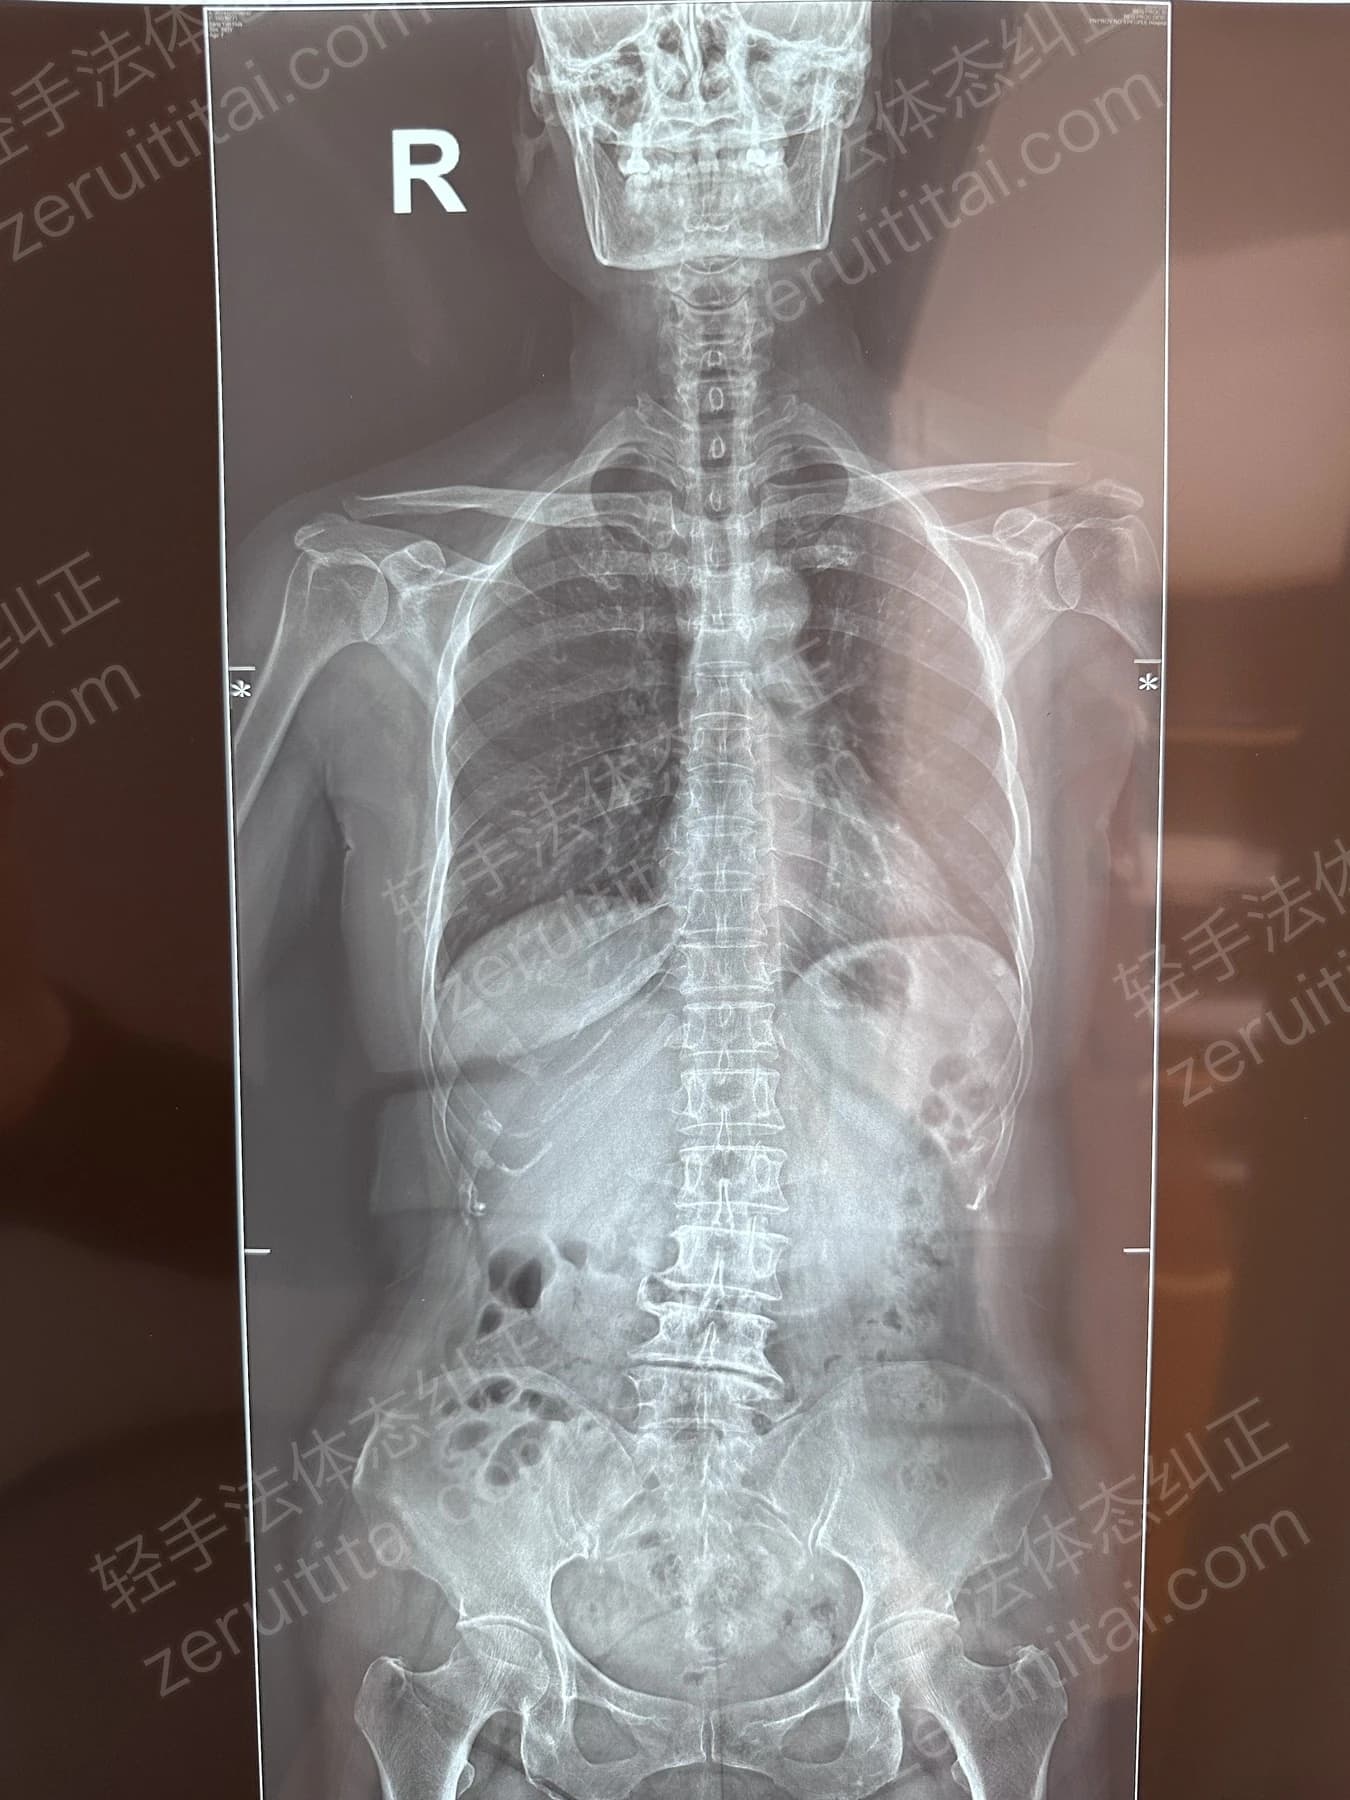

2022.12.26

第 3 次记录